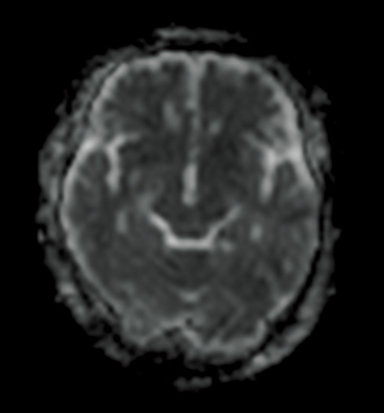

ADC map